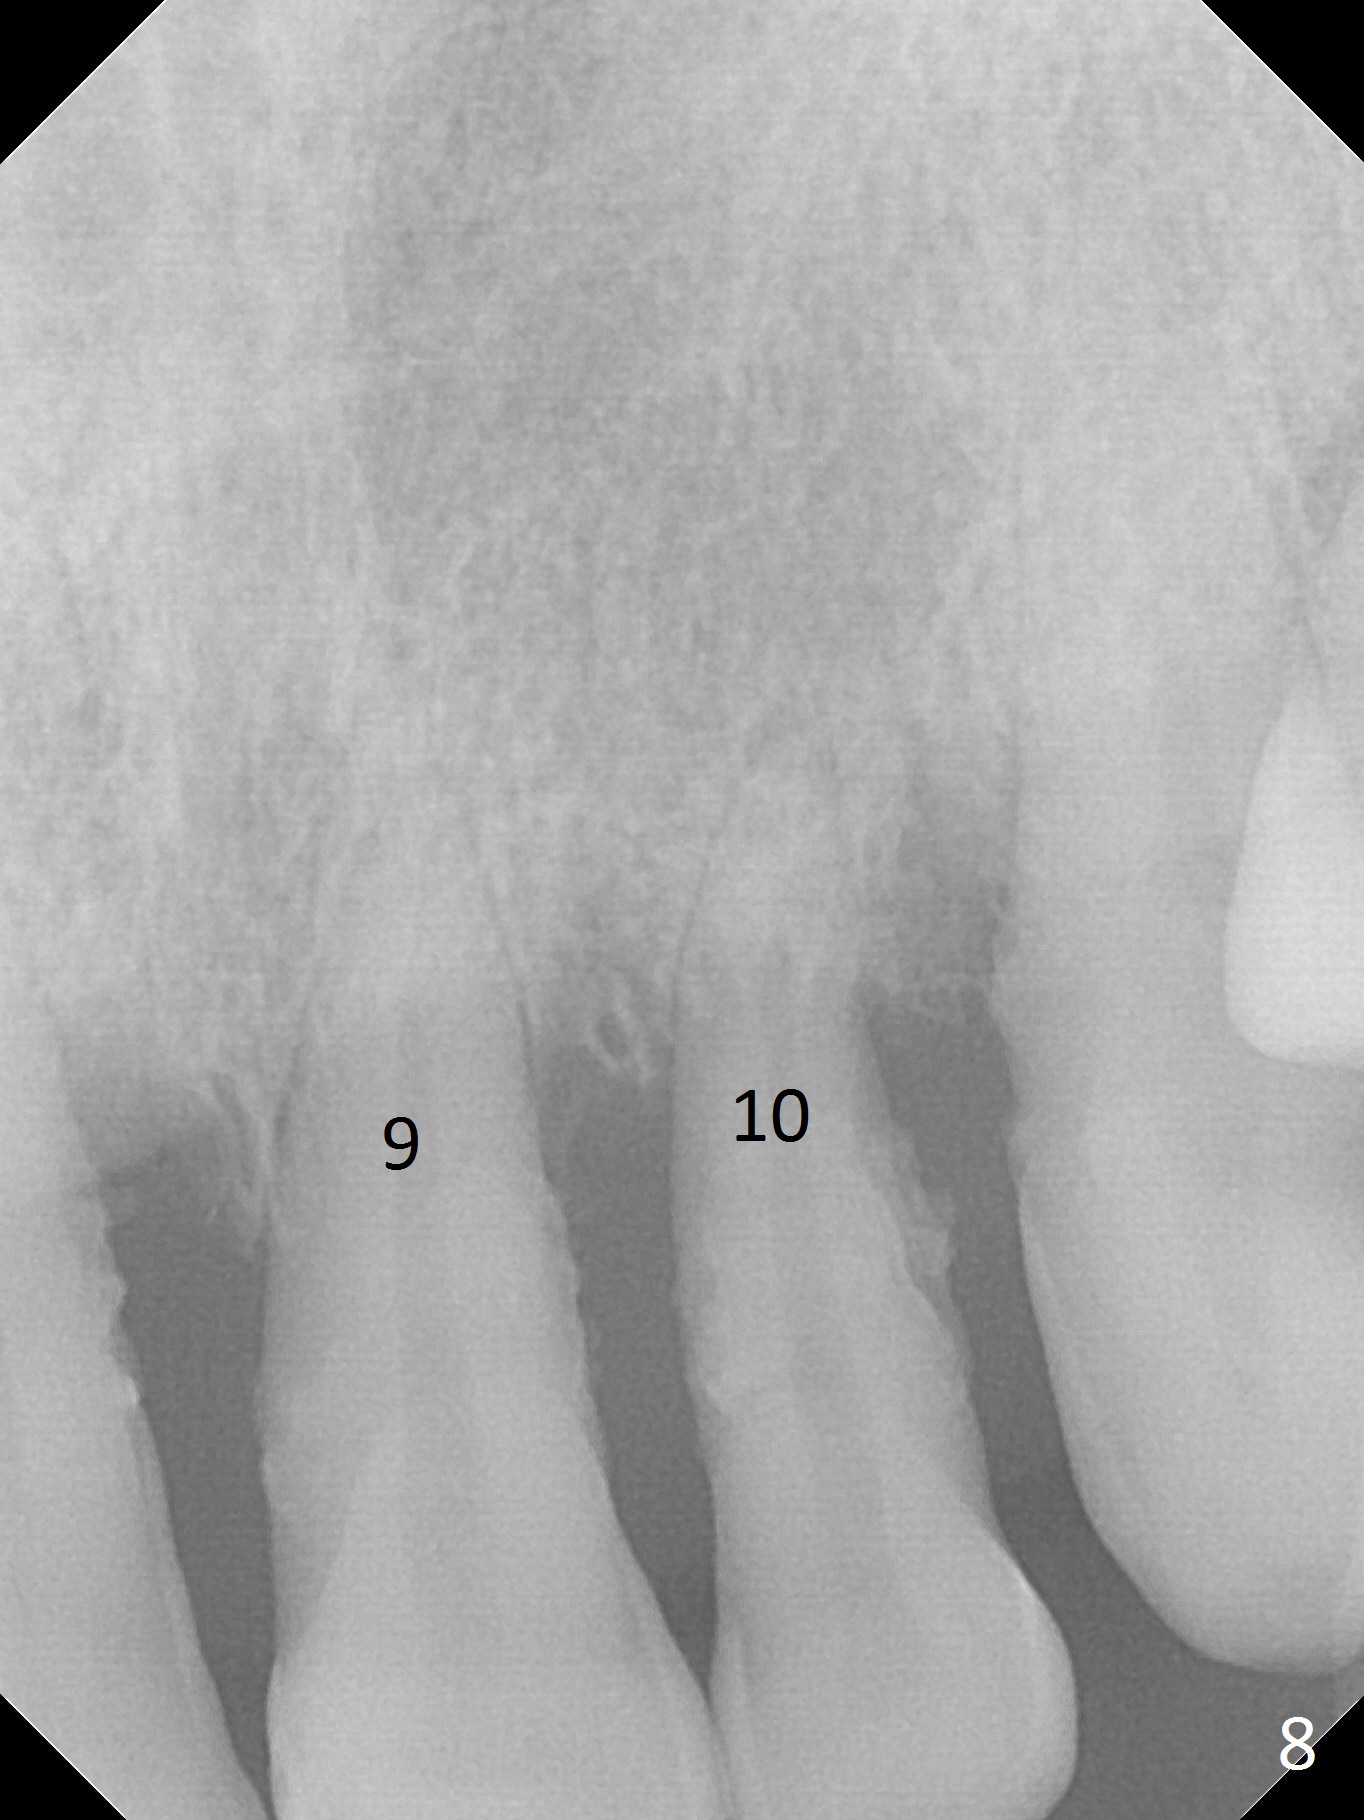

Class II Division II malocclusion (Fig.2,6) will make it difficult to restore #23-26 implant-supported FPD. Although the teeth #7-10 may need to be replaced later (Fig.7,8), enameloplasty will be conducted for #7-10 (Fig.9 white area; Fig.12 black circles (gross reduction)) prior to #23-26 extraction and implant placement (Fig.10). To be flexible in restoration (angulation) and possible future hybrid denture, 2-piece narrow implants will be placed (3.0 or 3.3 mm) instead of 1-piece ones. In fact CBCT shows that the narrowest regular implant (3.8 mm) can be placed in the lower anterior region (Fig.13-15).